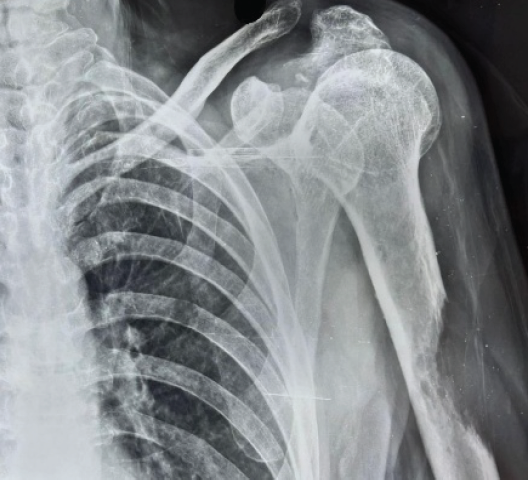

A 89-year-old male with a fracture left shaft of humerus.

Presentation

A 89-year-old male patient was referred from the oncology outpatient department (OPD) to orthopedics OPD with complaint of pain in the left shoulder. The patient was a known case of chronic myeloid leukemia and was on chemotherapy for 2 years.

Investigations

Plain radiograph of the left arm showed lytic lesion of the proximal shaft humerus (Fig. 5). Skeletal survey of the patient revealed multiple lytic lesions over the skull characteristic for multiple myeloma (MM). On further workup, Myeloma profile revealed a serum Calcium – of 7.7 mg/dL, serum beta-2 microglobulin – above 20,000 ng/mL, M band on serum protein electrophoresis.

Figure 5 : Plain radiograph of the left arm showing lytic lesion of the proximal shaft of humerus (89-year-old male with multiple myeloma). Skeletal survey revealed multiple lytic lesions over the skull characteristic of multiple myeloma involvement. The proximal humeral shaft location is the second most common site for long bone metastases and pathological fractures.